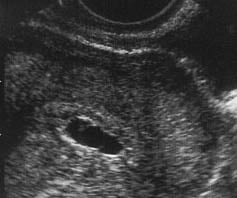

Gebelik kesesi ölçümü normal değerleri

Hafta

Ortalama

mm

5.0

1.0

5.5

1.3

6.0

1.7

6.5

2.0

7.0

2.4

7.5

2.7

8.0

3.1

8.5

3.4

9.0

3.8

9.5

4.1

10.0

4.5